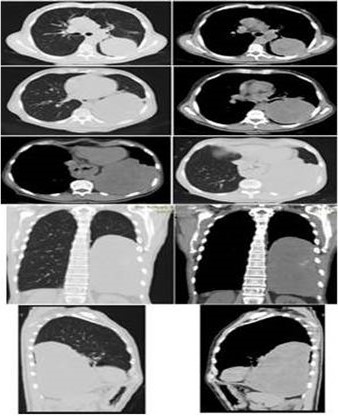

A la exploración física lo positivo en la esfera respiratoria encontramos a la percusión torácica matidez y a la auscultación murmullo vesicular abolido en el en el tercio inferior del hemitórax izquierdo. El resto del examen físico estaba dentro de lo normal. Los exámenes complementarios realizados mostraron resultados normales. Se solicita TC de tórax que reporta lesión de tejido blando redonda ovalada de contorno definidos con contacto pleural, que mide 19,8 cm x 15,5 cm, con desplazamiento de las estructuras cardio-mediastinales engrosamiento intersticial difuso con bandas atelectásicas en el lóbulo inferior izquierdo (Figura 2). Se programa el caso para cirugía, pero previamente se solicita estudio de funcionalismo funcional (espirometría) la cual reporta los siguientes valores: capacidad vital forzada (CVF) 75 % volumen espiratorio forzado en el 1° seg 70 % (FEV1), relación CVF y FEV1 75 % por lo que se interpreta un patrón espirométrico mixto debido a que se detectó obstrucción + restricción

Este tipo de neoplasia está relacionada con mutación genética de gen K-Ras, no con mutación de EGFR, y el estudio inmunohistoquímico es positivo con CK20 y puede no ser positivo con CK7 y TTF1, no se relaciona con la hiperplasia adenomatosa atípica y en los estudios de imágenes como la TC de pulmón se presenta como una imagen en patrón de consolidación, como en el caso que reportamos (8).